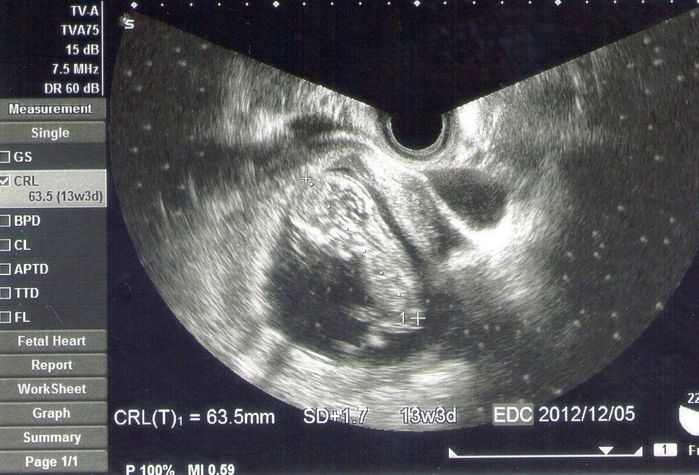

妊娠12週目のエコー写真 毎日吐いて体重減少

CRL=63.5㎜

画面の左側を向き、頭を上にした赤ちゃんが写っています。背骨とへその緒が見えました。くるくる動いてとってもかわいかったです。自分と赤ちゃんがつながっているのだと思うと、よい栄養を送ってあげなくちゃと思い、気が引き締まりました。